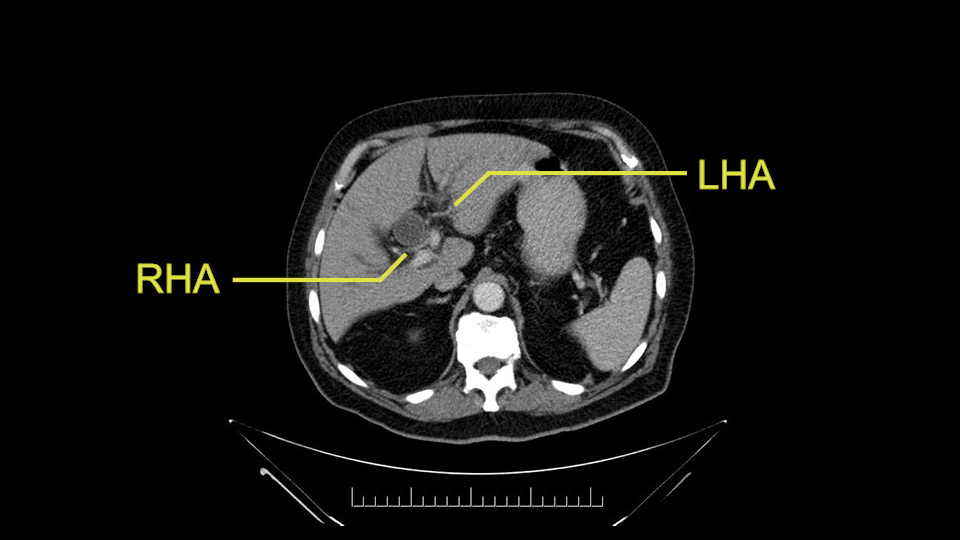

He has normal arterial anatomy: no accessory or replaced right hepatic artery, which is important because sometimes the right hepatic artery can come behind the neck of the pancreas and you have to be careful of that in a Whipple dissection.

Then you look for anomalies. The one you worry about the most doing a Whipple is a replaced or aberrant right hepatic artery coming off the SMA at its origin. So again, find the SMA. You can find it because the renal vein goes through it. Follow it up, up-up-up. Nothing coming off of there that I can see here. Nothing coming off of it, nothing coming off of it and just to confirm it, look at the celiac trfurcation. There’s the celiac, there’s the bifurcation, there's the splenic artery, hepatic artery. Make sure there’s a right, which there is here. The right usually goes under the bile duct: important when you’re going around the bile duct to do a Whipple. A replaced right goes under the portal vein and the bile duct way over here on the right. That’s about it.

The other slowing down moment would be the gastroduodenal artery. Confirming that the gastroduodenal artery is not a dominant artery supplying blood to the liver. Liver failure is something which we don’t want due to altered blood supply to the liver or hampered arterial blood supply to the liver. So I would dissect out the hepatic artery, the left and right branches very clearly. Put a bulldog clamp on the gastroduodenal artery, make sure that the perfusion of the liver is excellent on the right and left side, and then divide the gastroduodenal artery. I would avoid using crushing instruments or crushing clamps on the gastroduodenal artery because they have a tendency to shatter in patients who are old with friable vessels so you have to be careful and tackle it with the help of a 5-0 or a 6-0 prolene sutures. In younger patients, I would just apply clips and move on when it comes to dividing the gastroduodenal artery.

To plan a pancreatoduodenectomy, we start by reviewing the vascular anatomy, especially the origin of the celiac trunk, here, in front of the aorta, looking for any evidence of stenosis. In addition, we look at the origin of the superior mesenteric artery, to look for any branches, and any replaced right hepatic arteries coming from the superior mesenteric artery; which does occur in about 12% of the population.

First, the stenosis of the celiac trunk, which can be caused by arteriosclerosis, especially in a patient who is 83, or in patients who have arcuate ligament; we do see it, sometimes in much younger patients. In those cases, it may be that the circulation of the hepatic artery comes entirely from the gastroduodenal artery and its anastomoses, through the pancreaticoduodenal arteries, coming from the superior mesenteric artery. This means that before the gastroduodenal artery is ligated, we first clamp and wait 30 seconds to a minute, to feel and check the arterial inflow to the liver. If the pulse is diminished or there is a complete absence of the pulse, the surgery should be modified or probably a pancreatoduodenectomy cannot be done, because of the risk - when ligating the gastroduodenal artery - of causing fulminant hepatic ischemia postoperatively.

The second point about the vascular anatomy-, is to again look for right hepatic arteries in the hilum, coming from the superior mesenteric artery by palpating-through the Winslow Hiatus. Usually we will check for a pulse in the posterior aspect of the hepatic hilum, where a right hepatic artery should not usually be found. In this case, the precaution is to avoid an accidental ligation of the right hepatic artery that might jeopardize perfusion of the right lobe, or if there is a completely replaced hepatic artery that can put the liver circulation at risk.

I am a believer in pylorus preservation. And in this case I see no reason why that wouldn't be possible. Mobilize the duodenum, divide the gastroepiploic vessels and divide the duodenum. I try to divide it with a linear stapler about four centimeters from the pylorus to have adequate length for my GI anastomosis. This facilitates exposure of the head neck of the pancreas. I find the gastroduodenal artery. This patient has normal arterial anatomy. Always on every preoperative CT scan I look to see if there is a replaced right hepatic. In this case I did not see one. Regardless of how confident I am I always look carefully for variant anatomy. I always do a clamp test on the GDA before ligation. I doubly ligate the GDA with not just a tie but a suture ligature because of the risk of GDA blowout in patients with a leak.